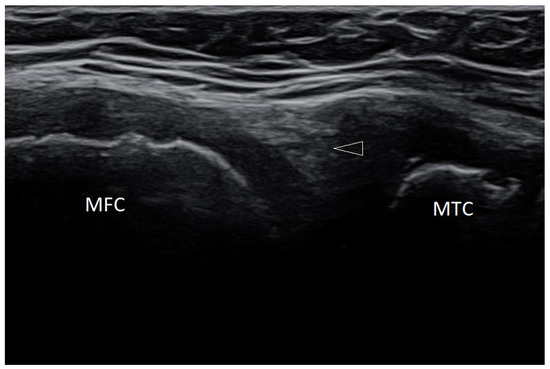

Basic Differences and Most Common Findings in Ultrasound Examinations of Musculoskeletal System in Children: A Narrative Literature Review

by Tomasz Poboży, Wojciech Konarski, Karolina Piotrowska-Lis, Julia Domańska, Kamil Poboży and Maciej Kielar

We present basic differences in the musculoskeletal ultrasound examinations between adults and children. Examiners who deal with adults on a daily basis have shared concerns about examining children. Such concerns may arise from the different approach to child ultrasounds, but they also come [...] Read more.

We present basic differences in the musculoskeletal ultrasound examinations between adults and children. Examiners who deal with adults on a daily basis have shared concerns about examining children. Such concerns may arise from the different approach to child ultrasounds, but they also come from differences in anatomical characteristics according to developmental age. We discuss the presence of growth plates, as well as non-mineralized parts of the bones. We also refer to the pathologies most often found in ultrasounds in early developmental stages. In the PubMed database, the set of keywords: “msk ultrasound in children”, “pediatric msk sonoanatomy”, “coxitis fugax”, “pediatric Baker’s cyst”, “Baker’s cyst ultrasonography”, “bone septic necrosis in ultrasonography”, “ultrasonography in juvenile idiopathic arthritis”, and “ultrasonography in juvenile spondyloarthropathies”, was used to identify a total of 1657 results, from which 54 was selected to be included in the article. We discuss the problem of osteochondritis dissecans, Osgood-Schlatter disease, examples of ligament injuries (especially in relation to the knee and ankle joints), exfoliation of growth cartilages, osteochondroma, exudates and inflammations affecting joints, and Baker’s cysts. In this way, we have collected useful information about the most common diseases of the musculoskeletal system in children. Full article